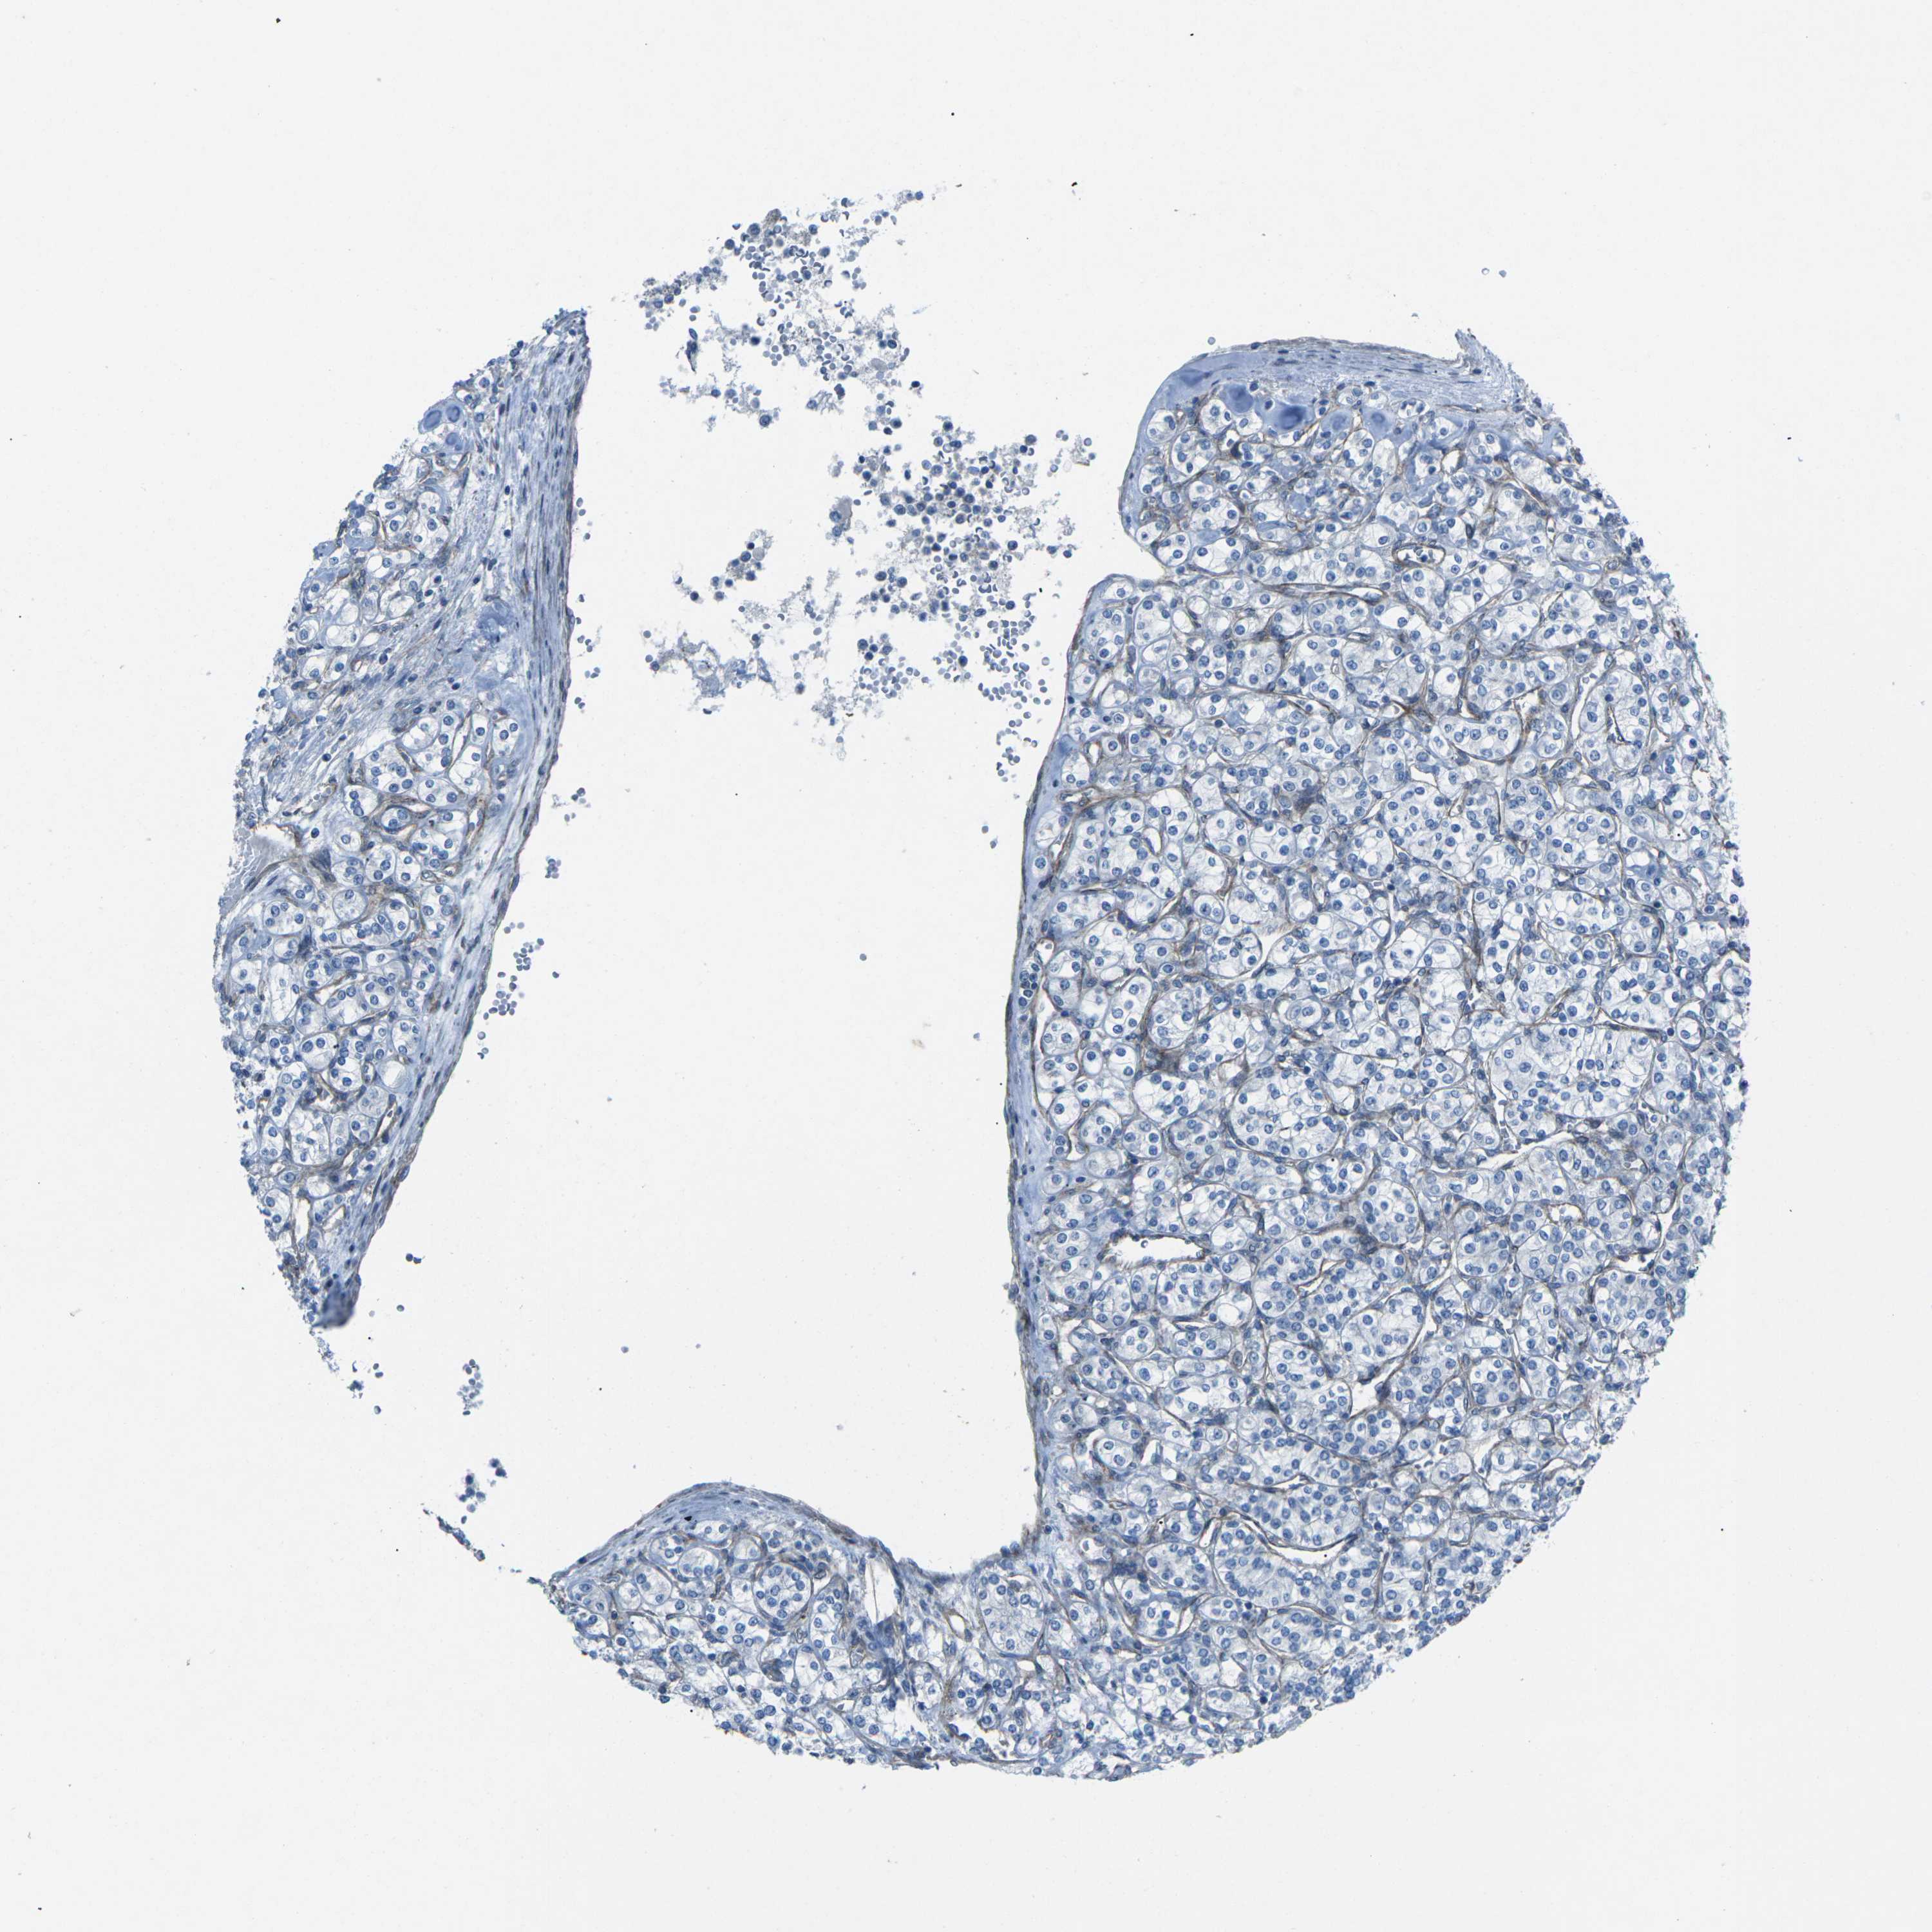

KIDNEY CHROMOPHOBE (TCGA) - Interactive survival scatter ploti

The Survival Scatter plot shows the clinical status (i.e. dead or alive) for all individuals in the patient cohort, based on the same data that underlies the corresponding Kaplan-Meier plots. Patients that are alive at last time for follow-up are shown in blue and patients who have died during the study are shown in red.

The x-axis shows the expression levels (FPKM) of the investigated gene in the tumor tissue at the time of diagnosis. The y-axis shows the follow-up time after diagnosis (years). Both axes are complimented with kernel density curves demonstrating the data density over the axes. The top density plot shows the expression levels (FPKM) distribution among dead (red) and alive patients (blue). The right density plot shows the data density of the survived years of dead patients with high and low expression levels respectively, stratified using the cutoff indicated by the vertical dashed line through the Survival Scatter plot. This cutoff is automatically defined based on the FPKM cutoff that minimizes the p-score. The cutoff can be changed by dragging the vertical line or by entering a cutoff value in the square labeled "Current cut-off".

Under the Survival Scatter plot the p-score landscape (black curve; left axis) is shown together with dead median separation (red curve; right axis). Dead median separation is the difference in median mRNA expression between patients who have died with high and low expression, respectively. It is calculated as follows: median FPKM expression of dead patients with high expression - median FPKM expression of dead patients with low expression. This is intended to aid the user in visually exploring custom cutoffs and the associated p-scores and dead median separation.

Individual patient data is displayed and can be filtered by clicking on one or more of the category buttons on the top of the page. Categories describing expression level and patient information include: high, low, alive, dead, female, male and tumor stages. The scale of the x-axis can be toggled between linear and log-scale by clicking on the "x log" button. Mouse-over function shows TCGA ID, patient information and mRNA expression (FPKM) for each patient.

& Survival analysisi

Kaplan-Meier plots summarize results from analysis of correlation between mRNA expression level and patient survival. Patients were divided based on level of expression into one of the two groups "low" (under cut off) or "high" (over cut off). X-axis shows time for survival (years) and y-axis shows the probability of survival, where 1.0 corresponds to 100 percent.

UTRN is not prognostic in Kidney Chromophobe (TCGA)

Best expression cut offi

Based on the FPKM value of each gene, patients were classified into two groups and association between prognosis (survival) and gene expression (FPKM) was examined. The best expression cut-off refers the FPKM value that yields maximal difference with regard to survival between the two groups at the lowest log-rank P-value. Best expression cut-off was selected based on survival analysis .

When clicking on this number, the vertical dashed line indicating cut-off, the interactive survival plot, and the Kaplan-Meier curve will be adjusted to show results based on the best expression cut-off.

: 13.12

Median expressioni

Median expression refers to the median FPKM value calculated based on the gene expression (FPKM) data from all patients in this dataset. When clicking on this number, the vertical dashed line indicating cut-off, the interactive survival plot, and the Kaplan-Meier curve will be adjusted to show results based on the median expression.

: N/A

Median follow up timei

Median follow up time refers to the median time (years) after diagnosis with this type of cancer, based on clinical data from all patients in this dataset.

P scorei

Log-rank P value for Kaplan-Meier plot showing results from analysis of correlation between mRNA expression level and patient survival.

N/A

5-year survival highi

5-year survival for patients with higher expression than the expression cutoff.

For melanoma and glioma, 3-year survival is shown.

5-year survival lowi

5-year survival for patients with lower expression than the expression cutoff.

Average pTPM 13.7

Number of samples 64